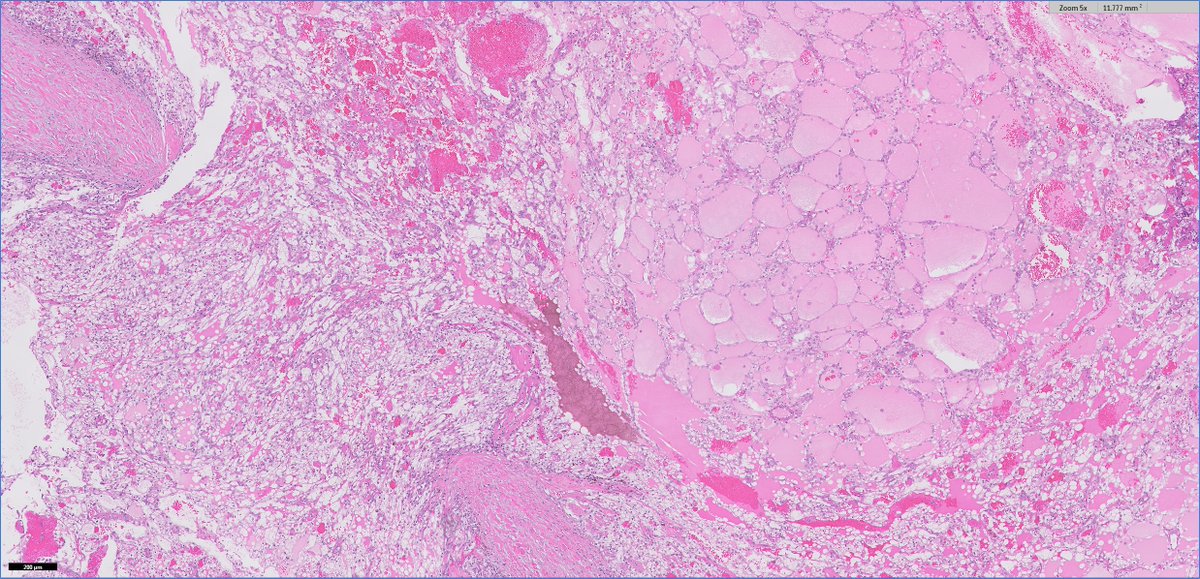

50yo ♀ thyroid, 1st impression? A) PTC, diffuse sclerosing variant B) Hashimoto thyroiditis, fibrosing variant C) Riedel thyroiditis 🔬virtualpathology.leeds.ac.uk/slides/library… #Thyroid #EndoPath #ENTPath #PathTwitter #Pathology #Pathologists

DrCycloPath's tweet image. 50yo ♀ thyroid, 1st impression?

A) PTC, diffuse sclerosing variant

B) Hashimoto thyroiditis, fibrosing variant

C) Riedel thyroiditis

🔬virtualpathology.leeds.ac.uk/slides/library…

#Thyroid #EndoPath #ENTPath #PathTwitter #Pathology #Pathologists